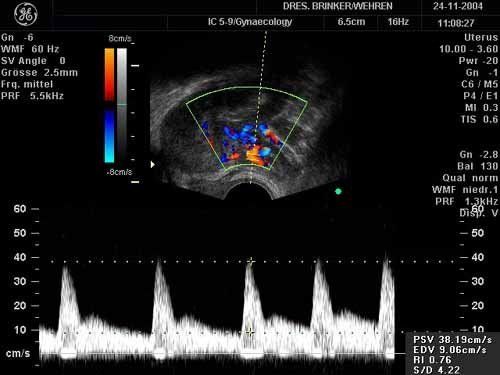

Bei der Krebsvorsorgeuntersuchung wird eine Tastuntersuchung der Inneren Geschlechtsorgane (Gebärmutter und Eierstöcke) vorgenommen. Weitaus mehr Informationen über Veränderungen dieser Organe erhält man durch die bildgebende Ultraschalluntersuchung mit einem Vaginalschallkopf. Dadurch können auch kleinste Tumoren, Zysten, etc. entdeckt werden, die sich dem Tastbefund entziehen - sei es, weil der Leibesumfang der Patientin diesen unsicher macht oder weil die Veränderung (z. B. eine Zyste des Eierstocks) überhaupt nicht tastbar ist. Insbesondere Zysten in den Eierstöcken können im Frühstadium kaum anders gefunden werden, eine Behandlung erfolgt dann oft später als möglich gewesen wäre. Die Eierstock-Zyste der älteren Frau ist ggf. gar das einzige Frühsymptom des Eierstock-Krebses und ihr rechtzeitiger Nachweis (lange bevor die Frau etwas spürt) dann lebensrettend ! Bei jüngeren Frauen lassen sich z.B. Erkrankungen wie Endometriose und „Perlenketten-Eierstöcke“ (PCO) erkennen, die eine Unfruchtbarkeit zur Folge haben können, ohne Beschwerden zu machen. In der Gebärmutter können Muskelknoten (Myome) erkannt werden. Durch Beurteilung der Gebärmutterschleimhaut läßt sich oft ein überschießendes Wachstum feststellen, bevor sich die Schleimhaut bösartig entwickelt.

Mit einer Untersuchung der Harnblase haben wir schon einige Blasentumore entdeckt. Bei gleichzeitigem Pressen kann das Ausmass einer Blasensenkung abgeschätzt werden, die oft für eine Harninkontinenz verantwortlich ist.